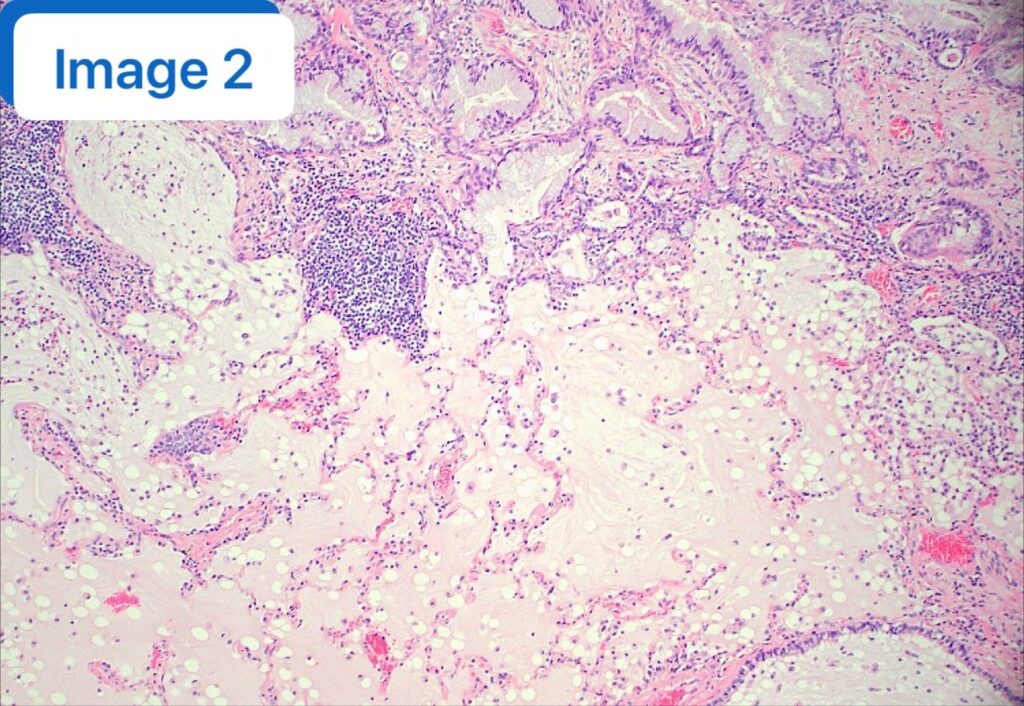

🔪 【反转与真相】 患者随后接受了手术切除,但大体标本的切片却讲述了一个完全不同的故事。 显微镜下呈现出了 CMPT 的经典特征(见附图):

- 丰富的黏液池(图2);

- 表面被覆纤毛柱状细胞,且存在基底细胞层;

- 无细胞异型性,无间质浸润。